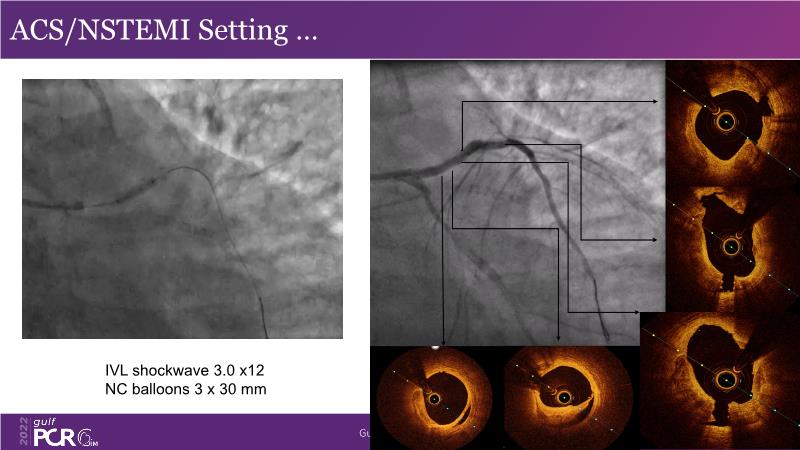

Optimal PCI in patient with long calcified lesion

In this session, follow a LIVE case from the Chest Diseases Hospital in Kuwait and learn what the best strategy is to treat patients who present with a very long calcified coronary artery lesion, as well as how to select the best device and which different types of stents can be used.

- To understand value of intracoronary imaging in patient treatment